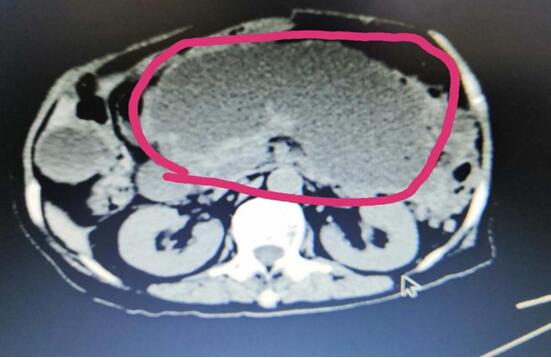

患者A,女,72歲,1年前因急性出血壞死性胰腺炎,曾行腹腔鏡下壞死胰腺組織清創(chuàng)+外引流術(shù),術(shù)后出現(xiàn)急性胰腺假性囊腫,囊腫越來越增大,以至于病人不能做下蹲和彎腰動(dòng)作,給生活造成極大不便。本次患者因急性腹痛入院,入院診斷為:胰腺巨大假性囊腫并發(fā)出血,重癥胰腺炎清創(chuàng)術(shù)后。

(術(shù)前腹部CT顯示胰腺巨大假性囊腫)